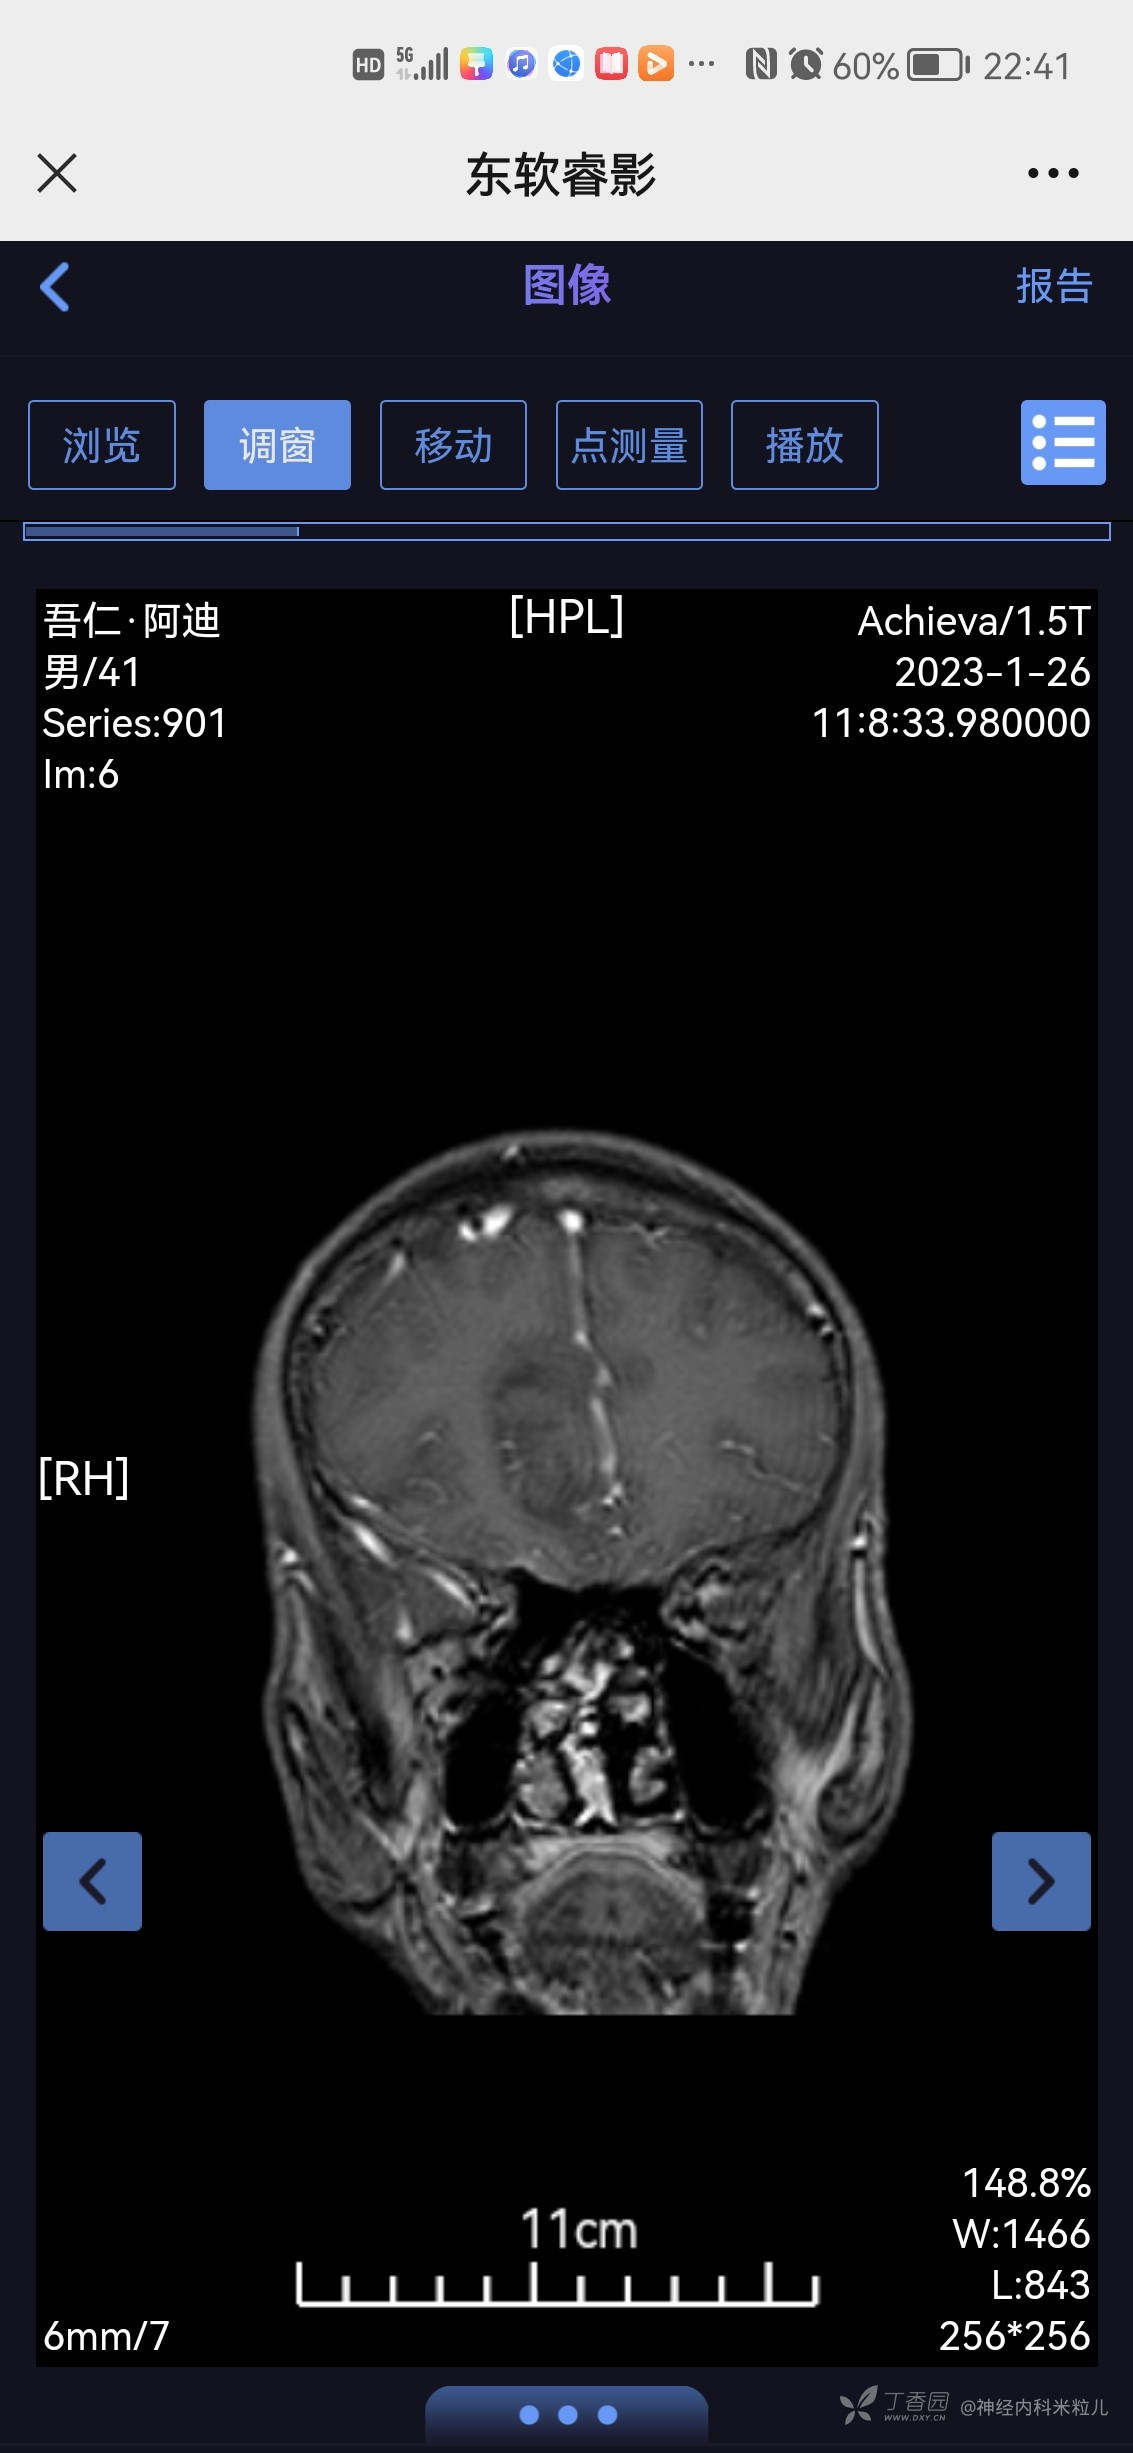

青鹊词等 3人推荐患者家属及本人共诉:于1月6日左右突然出现头痛,呈间断搏动性疼痛,以额部疼痛为主,休息后略好转,白天头痛明显,夜间尚可,并伴有发热,未测体温,发热3天,呈持续发热,并伴有腹泻2天,呈水样便,每日7-8次,无黑便、无血便。就诊当地镇医院,具体诊断及治疗不详,随后症状自行改善,13日患者因手抖,心悸不适来我院内分泌住院治疗诊断甲亢,并给于相应治疗:甲巰咪唑30mg一日次口服,利法沙班15mg一日一次口服,普萘洛尔10mg一日三次口服,查2023年1月18日我院头颅核磁提示:颅内多发异常信号,考虑:感染性病变,建议增强检查。随后患者出院,头痛未再次发作,故今日为进一步查明病因来我院,门诊以“颅内感染、甲亢”收住我科,病程中患者有发热,有头痛、无头晕、无恶心、呕吐、无乏力、有多汗、有心悸、无心前区疼痛、无腹泻,无黑便、无脓血便、饮食睡眠可,近期有体重下降,具体不详。

2023年1月18日我院头颅核磁提示:颅内多发异常信号,考虑:感染性病变,建议增强检查。}